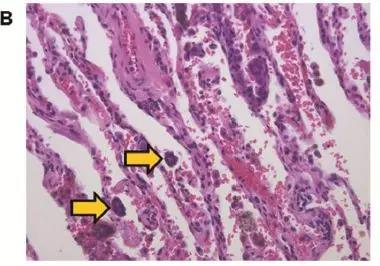

图B,病理检查发现肿瘤周边有1-4个癌细胞或癌巢,属于低STAS

图C,病理检查发现肿瘤周边有超过5个癌细胞或癌巢,属于高STAS